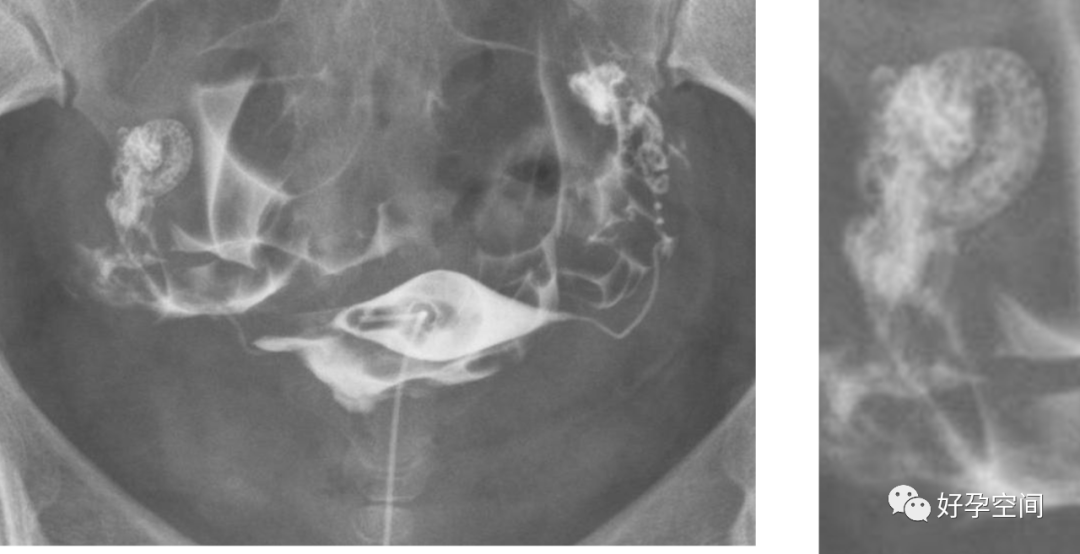

5、正常输卵管走行:正常的输卵管是从子宫角的尖端起,呈自然流线形,输卵管走行不固定,两侧输卵管不一定对称,输卵管活动度很大,走行分四型:(1)上行,和宫体连接呈缠绕状,在子宫底两侧弯弯曲曲上行,壶腹部远段和伞部向下屈曲。(2)反向走行,一侧上行,另一侧下行。(3)下行,和宫体连接呈缠绕状,在子宫两侧弯弯曲曲下行,壶腹部远段和伞部向上屈曲。(4)水平走行,在宫底水平向两侧呈伸展状。

双侧输卵管上行

双侧输卵管反向走行(一侧上行,对侧下行)